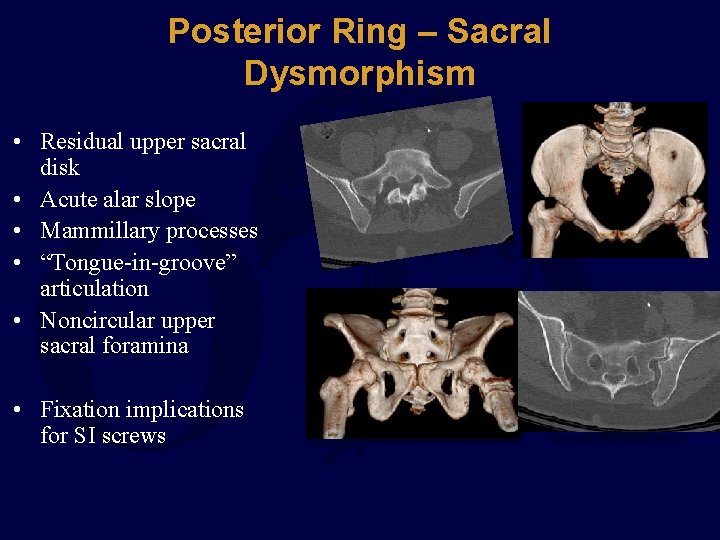

Posterior Ring – Sacral Dysmorphism • Residual upper sacral disk • Acute alar slope • Mammillary processes • “Tongue-in-groove” articulation • Noncircular upper sacral foramina • Fixation implications for SI screws